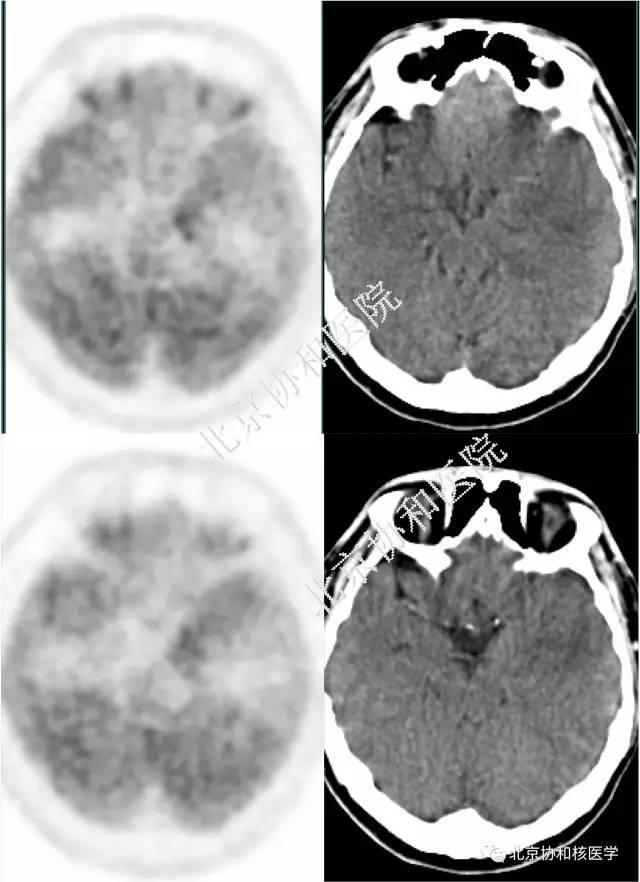

【病例】PET\/CT,头痛的脑病变!

640x882 - 54KB - JPEG